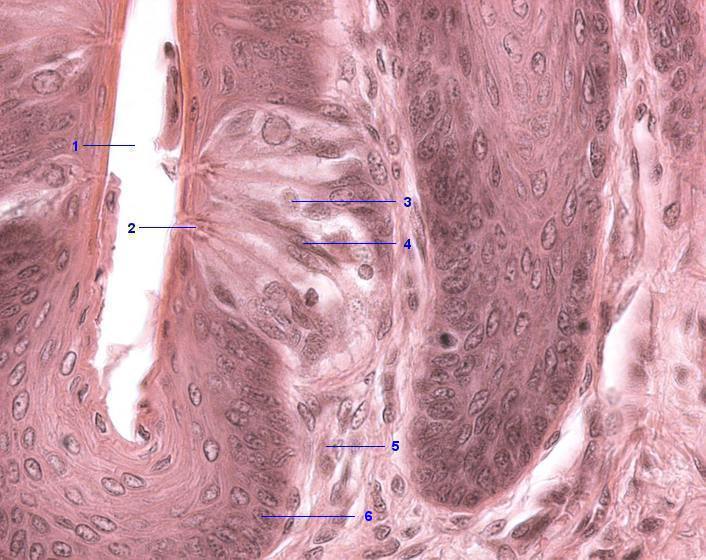

1 Papillengraben

2 Geschmacksporus

3 Helle Zelle (Sinneszelle)

4 Dunkle Zelle (Stützzelle)

5 Lamina propria

6 Lamina epithelialis, Stratum basale